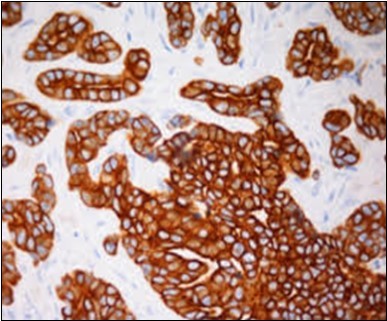

Figure 13.Immune reactivity to CK6 in eccrine porocarcinoma(25).

Immune reactivity to CK6 in            eccrine porocarcinoma(25).